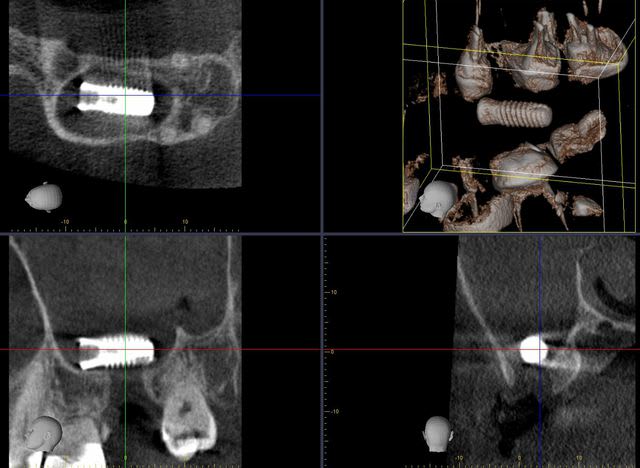

1&2: prélèvement sanguin pour centrifugation et réalisation de membranes de PRF

3: vue occlusale: plus ou pas d'écoulement purulent

le patient a été placé sous orelox depuis samedi avec pulvérisation nasale 3x/j d'actisoufre

4: incision décalée en palatin par rapport au trou de la cbs (pas trop car après il y a risque de nécrose)

5: en général, il ya décollement assez facile entre la membrane de schneider et le palais.

1&2 : réalisation à l'aide d'une tréphine de la fenêtre vestibulaire pour aller plus vite et surtout pour pouvoir réutiliser plus tard ce petit bloc osseux.

( vous verrez plus atrd à quoi ça sert)

3: fenêtre et CBS bien visibles

après avoir copieusement irrigué le sinus avec sérum-phy puis avec de la bétadine...

1: suture de la déchirure membranaire

2: PRF

3: PRF en recouvrement sur l'ancienne perforation

4: deuxième couche de métrocol

5-6-7: un tout petit peu de biomat pour remplir (mais sans excès) le petit volet osseux de la fenêtre latéral est déplacé pour servir de greffon osseux sur l'ancienne CBS à la manière d'un bouchon.

8: membrane cellulaire de recouvrement par dessus la fenêtre d’accès puis stabilisation par des pins.

9: sutures finales

10: le vilain garçon...

11-12: RX avant-après